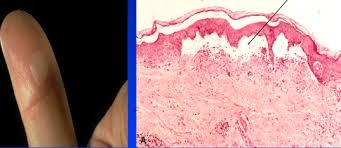

Necrosis Enzymatic degradation of a cell resulting from exogenous injury. Characterized by enzymatic digestion and protein denaturation, with release of intracellular components. Inflammatory. Morphologically occurs as coagulative (heart, liver, kidney), liquefactive (brain), caseous (tuberculosis), fat (pancreas), fibrinoid (blood vessels), or gangrenous (limbs, GI tract).

Cell injury Reversible Irreversible Cellular swelling Plasma membrane damage Nuclear chromatin clumping Lysosomal rupture ↓ATP synthesis Ca2+ influx→oxidative phosphorylation Ribosomal detachment Nuclear pyknosis, karyolysis, karyorrhexis Glycogen depletion Mitochondrial permeability Fatty change

Inflammation Characterized by rubor (redness), dolor (pain), calor (heat), tumor (swelling), and functio laesa (loss of function). Fluid exudation ↑vascular permeability, vasodilation, endothelial injury. Leukocyte activation Emigration (rolling, tight binding, diapedesis); chemotaxis (bacterial products, complement, chemokines); phagocytosis and killing. Fibrosis Fibroblast emigration and proliferation; deposition of ECM. Acute Neutrophil, eosinophil, and antibody mediated. Chronic Mononuclear cell mediated: Characterized by persistent destruction and repair. Granuloma––nodular collections of epithelioid Granulomatous diseases: TB macrophages and giant cells. (caseating), syphilis, leprosy, Resolution Restoration of normal structure. Bartonella, some fungal Granulation tissue––highly vascularized, fibrotic. pneumonias, sarcoidosis, Abscess––fibrosis surrounding pus. Crohn’s disease. Fistula––abnormal communication. Scarring––collagen deposition resulting in altered structure and function.